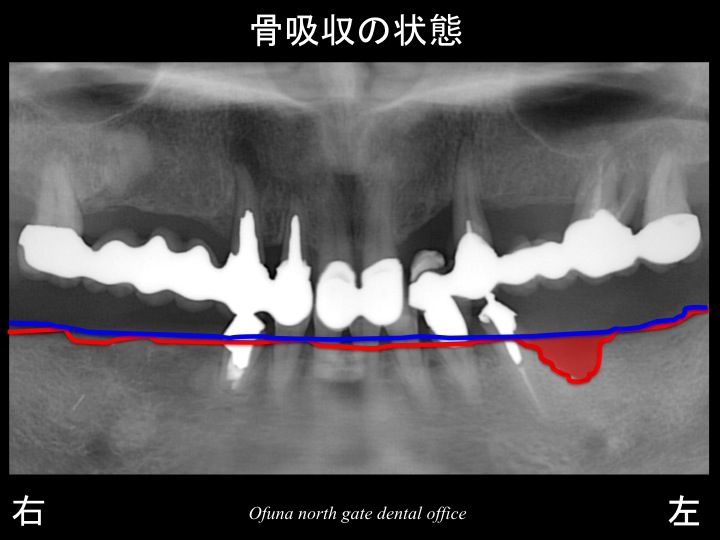

いつものように 骨吸収の状態を分かりやすくするために

下顎の 骨吸収の状態を線で書いたのが以下のレントゲンになります。

青線が骨吸収を起こす前の骨の位置です。

赤線は、現在の骨の位置です。

下顎左側の歯根破折 を起こしていた部位では、骨吸収が起こっています。

さらに わかりやすくするために、

骨吸収部位を赤色で表示します。

さらに骨吸収が大きいのが分かるかと思います。